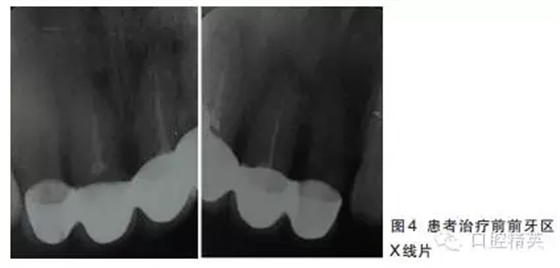

12~22烤瓷聯(lián)冠修復(fù),冠邊緣不密合,齦緣外形不協(xié)調(diào),牙齦紅腫,22烤瓷冠崩瓷。根管治療不完善,牙齦根尖部位有瘺管,X線影像顯示11、21根尖有陰影。